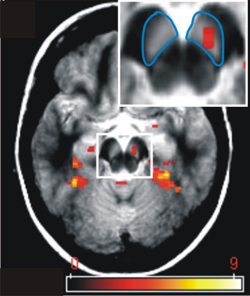

FMRT-Aktivierung: Dargestellt ist die Aktivierung der Substantia nigra/ Area tegmentalis ventralis des Mittelhirns. Diese Region ist beteiligt an der Regulation von Motivation und Verarbeitung von Belohnungserwartung. Die Substantia nigra/ Area tegmentalis ventralis ist blau markiert und die mittels funktioneller Magnetresonanztomographie (fMRT) gemessene Aktivierung ist in rot dargestellt.

Die Probanden nahmen in einer Reihe von Experimenten teil. In einer ersten Untersuchung wurde getestet, ob das Gehirn neue Information gegenüber bekannter Information bevorzugt, selbst wenn die bekannte Information selten oder emotional negativ ist. Den Teilnehmern dieser Studie wurden Bilder von Außenaufnahmen und Bilder von männlichen Gesichtern dargeboten, während ihre Gehirnaktivität mittels funktioneller Magnetresonanztomographie (fMRT) gemessen wurde. Dabei wurden einige der Bilder, auf denen zum Beispiel ein erzürntes Gesicht oder ein Autounfall zu sehen war, selten wiederholt dargeboten und andere Bilder stellten jeweils neue neutrale Gesichter oder Szenen dar. Die Substantia nigra/ Area tegmantalis ventralis des Mittelhirns reagierte ausschließlich auf neue Bilder, jedoch nicht auf wiederholte seltene oder emotionale Bilder.

Im zweiten Experiment wurden bekannte Bilder entweder im Kontext mit neuen Bildern oder im Kontext mit sehr bekannten Bildern dargeboten. Ebenfalls mittels fMRT wurde dabei untersucht, wie relative Neuheit die Gehirnaktivität in der Substantia nigra/ Area tegmentalis ventralis beeinflusst. Es konnte gezeigt werden, dass die Aktivierungsstärke in dieser Region abnimmt, je bekannter die gezeigten Bilder sind, unabhängig davon, in welchem Kontext sie gezeigt wurden.